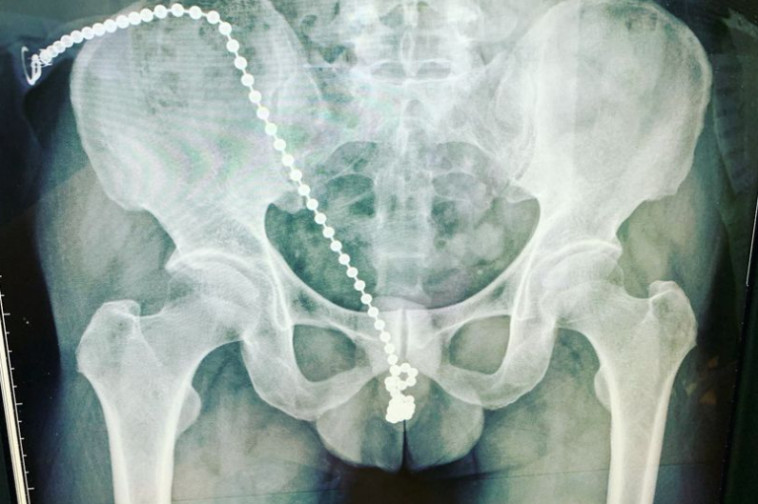

צילום הרנטגן של האיש

צילום הרנטגן של האיש | צילום: צילום מסך פייסבוק

לאחר שהגיע לשיא מטכניקת האוננות המשונה, הבחור נרדם ומאוחר יותר התעורר מכאבים בלתי נסבלים. החרוזים של השרשרת הוטבעו בתוך איבר מינו, והוא לא הצליח להסיר אותם מחשש שייפתע עוד יותר. הדבר אף מנע ממנו להטיל שתן.

המטופל המודאג התייעץ עם הרופאים בבית החולים ותהה מה יוכל לעשות כדי לצאת מהמצב המתסכל והמביך. גאו וויצ'אנג, האורולוג שטיפל החולה, הסביר: "המטופל לא הצליח להוציא את השרשרת מתוך השופכה, הוא כבר נפצע ולא רצה לגרום לעצמו עוד נזק". עוד הסביר הרופא כי בנסיבות רגילות, השרשרת הייתה אמורה להחליק החוצה בקלות, אך צינורית השופכה של האיש התהדקה עקב מתח.

האורולוג הוסיף כי האיש סבל מ"אי נוחות חמורה" והחרוזים השפיעו על העצבים העדינים באיבר המין וגרמו לו לתחושה של "התחשמלות". לאחר ניסיונות רבים לסייע למטופל, לא נותרה לצוותים ברירה אלא לנתח אותו ולחתוך את איבר מינו ולהוציא את השרשרת לפני שייגרם נזק רב יותר לשופכה.